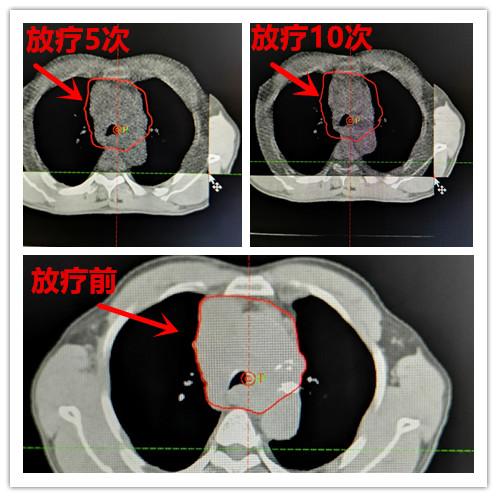

CT定位机下定位,并将影像传至放疗计划系统,医师按照治疗标准给予勾画靶区,再经物理师做出放疗计划。放疗5次肿瘤开始缩小,杨先生可以平躺睡觉了,放疗10次,病灶继续缩小,杨先生憋喘症状完全缓解,头面部肿胀基本消失,明显改善了病人的生活质量。杨先生全程治疗顺利,病情一天天好转,治疗结束后,病人已恢复正常,生活质量明显提高。

患者放疗5次、10次后,肿瘤明显缩小